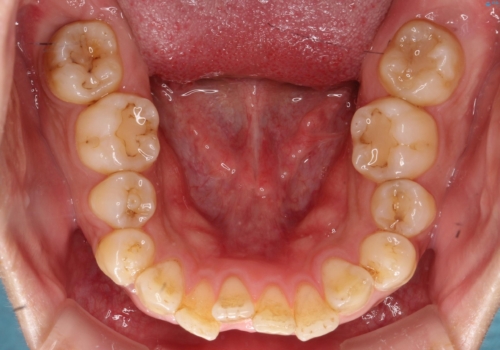

- 主訴:学生時代に矯正治療したが、後戻りしてしまった。上下前がのガタつきを治したい。

ワイヤー矯正(審美装置)非抜歯 治療期間:1年8か月

一日に物を口にする回数が多い方はマウスピース矯正における推奨装着時間を守ることや、その都度歯磨きをすることが難しいため、ワイヤー矯正での治療となりました。